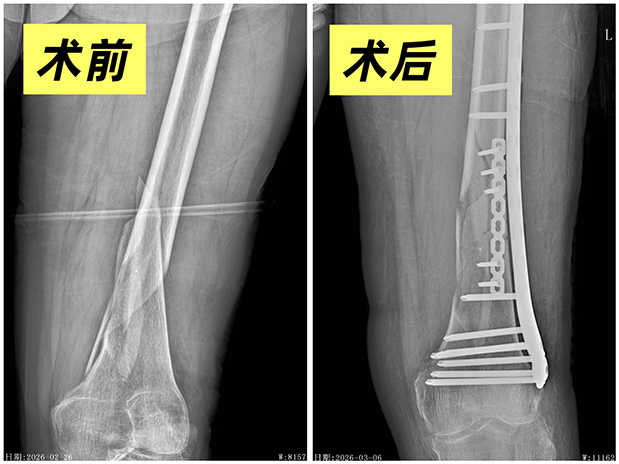

手术台上,曹家俊主任医师主刀,王凤民主任医师、汪林副主任医师及王汉全住院医师担任助手,器械精准稳定。术中可见,丁某左股骨远端粉碎性骨折,骨折端分离移位明显,复位难度极大。曹家俊凭借多年临床经验,小心翼翼清理骨折碎片、精准对齐骨折端,采用重建钢板+锁定钢板进行内固定,每一个动作都细致入微、精益求精。

90分钟后,最后一颗螺钉固定到位,监测仪器显示生命体征平稳,手术圆满成功。

3月14日,经过11天的精心治疗与护理,丁某顺利出院。出院复查X线片显示,其骨折对位良好、内固定在位,左足趾活动与感觉正常,末梢血运良好。“出院后会按时复查,认真做康复训练。”丁某的家属再三致谢。